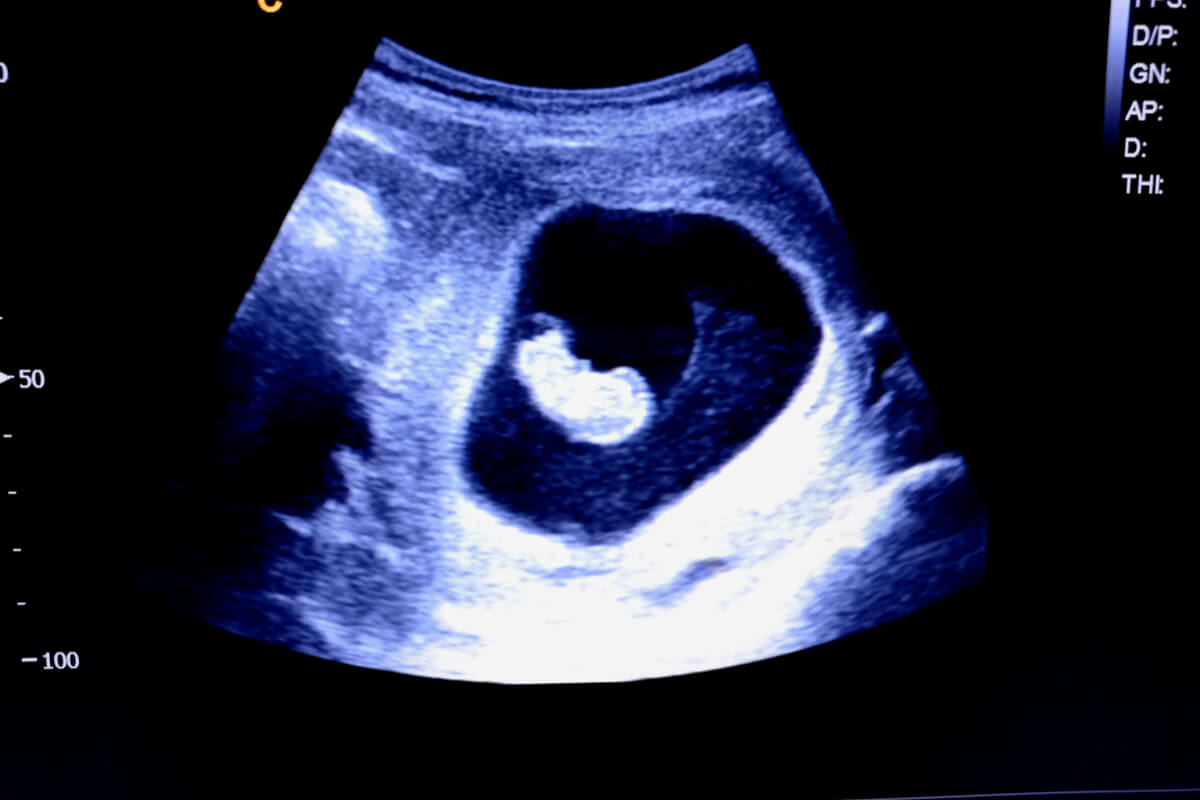

This strategy makes it possible to predict the sex of the baby from the first ultrasound scan, as it’s based on the location of the placenta and chorionic villi from the sixth week of gestation.

To determine the location of the placenta it’s necessary for the mother to undergo a Doppler ultrasound from the sixth week of gestation. This will show a bright area around the gestational sac, which is the place where this organ will grow. To determine whether it’s on the right or on the left, it’s necessary to take into account the mirror effect of this study.